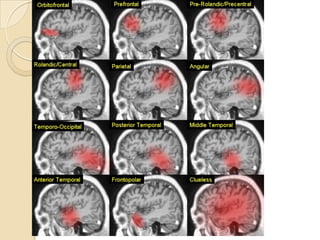

Acute ischemic stroke

 A novel application of MRA is to guide acute

stroke intervention potentially.

 MRA can be a predictor of clinical outcome in

acute ischemic pt. undergoing thrombolysis with

IV rtPA in window period. ( Marks et al 2008).

 The Boston scale ( BASIS) is a classification tool

to help predict outcomes in acute stroke by

using MRA study. ( Torres-Mozqueda et al 2008)